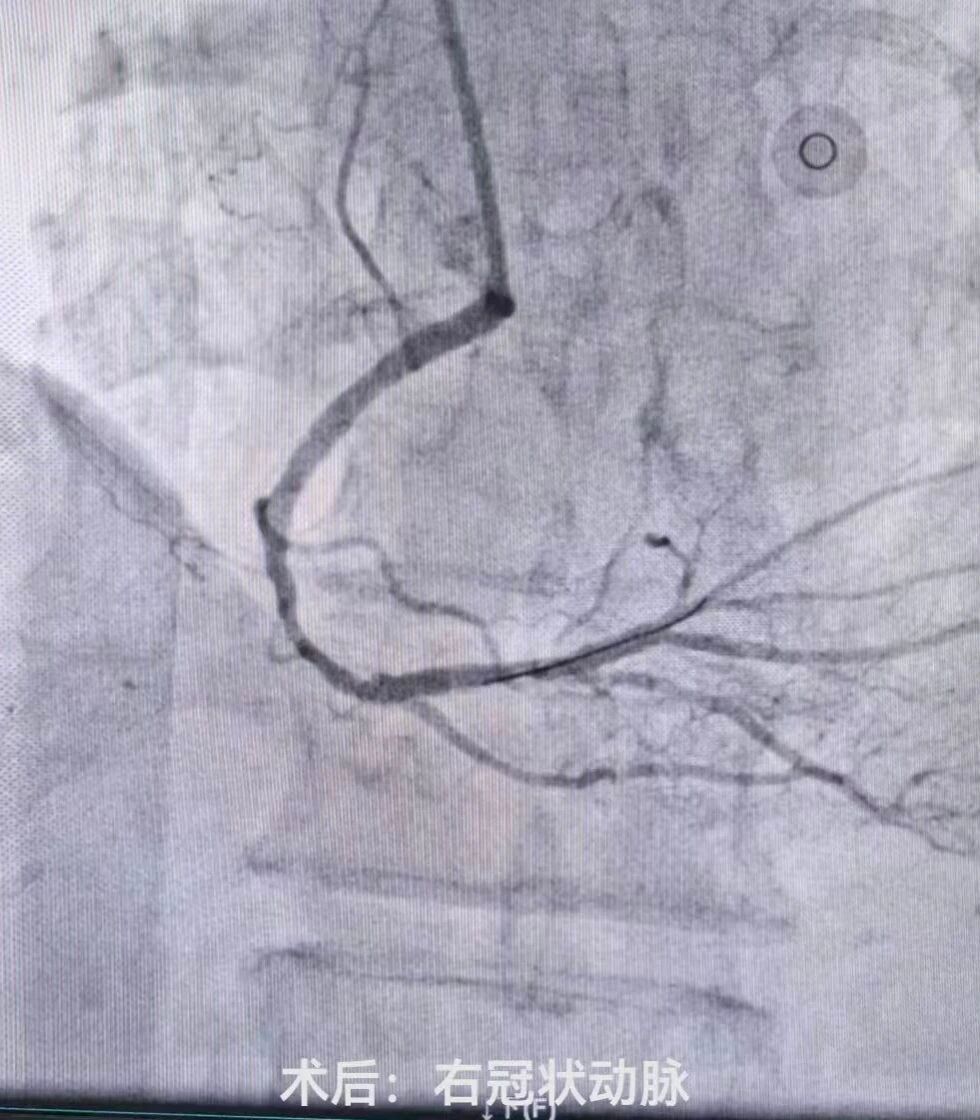

介入室内,医护团队严格遵循标准化操作流程,消毒、穿刺、造影等步骤一气呵成。冠状动脉造影显示心脏三支血管均有严重狭窄,其中两根主要血管均有95%以上的堵塞,患者已出现心力衰竭表现,生命危在旦夕,只有一次性处理两处严重狭窄病变才能为患者带来生的希望。刘晓建主任带领的介入团队凭借丰富的临床经验和精湛的介入技术预判手术风险,勇担重任,术中认真仔细操作,快速高效的同时完成了左前降支(LAD)、右冠状动脉(RCA)球囊扩张及支架植入术。随着支架成功释放,闭塞的血管瞬间恢复通畅,心肌供血得以重建,患者胸闷、胸痛症状较前明显缓解,生命体征逐渐平稳。

术前术后对比